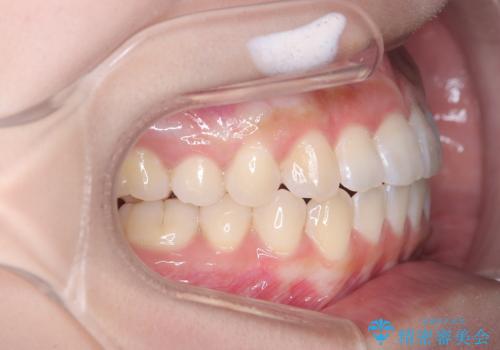

翼状捻転と叢生を矯正で改善

- 治療計画

治療では、審美ワイヤーを使用し、目立ちにくく配慮しながら矯正を進めました。上顎にリンガルアーチと矯正用アンカースクリューを用いて臼歯部を安定的に遠心移動させ、歯列全体のスペースを確保しました。その後、回転していた前歯を正しい位置に配列し、全体的な歯並びの改善を行いました。治療中は、装置の適切な管理と口腔衛生を徹底することが重要でした。結果として、見た目だけでなく機能的にも優れた歯列を実現することができ、患者様にもご満足いただけました。